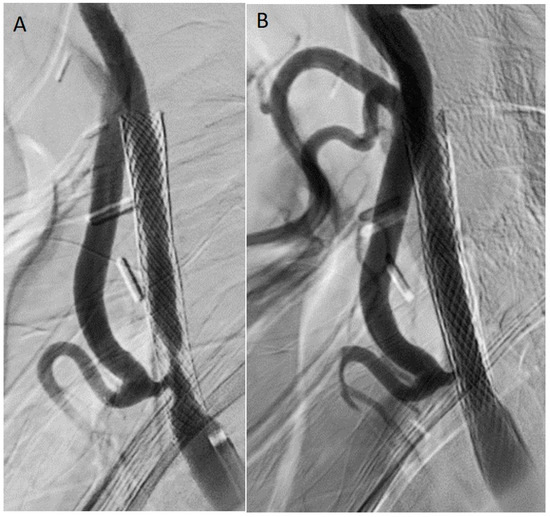

Carotid Restenosis: Incidence, Pathophysiology and Therapeutic Options

Restenosis after carotid endarterectomy and carotid artery stenting remains the main complication after both surgical and endovascular treatment of carotid stenosis, with a 2-year restenosis rate of 6–12%. Complex inflammation processes are the cause of early (<2 years) and late (>2 years) restenosis [...] Read more.

Restenosis after carotid endarterectomy and carotid artery stenting remains the main complication after both surgical and endovascular treatment of carotid stenosis, with a 2-year restenosis rate of 6–12%. Complex inflammation processes are the cause of early (<2 years) and late (>2 years) restenosis and principal systemic risk factors are female gender, hypertension, diabetes, dyslipidemia, and smoking. Non-procedural treatment includes lifestyle modifications and best medical therapy. The procedural treatment, considered mostly for symptomatic patients, includes different open and endovascular techniques. The management should be personalized according to patient and plaque characteristics. Full article

Show Figures

Graphical abstract